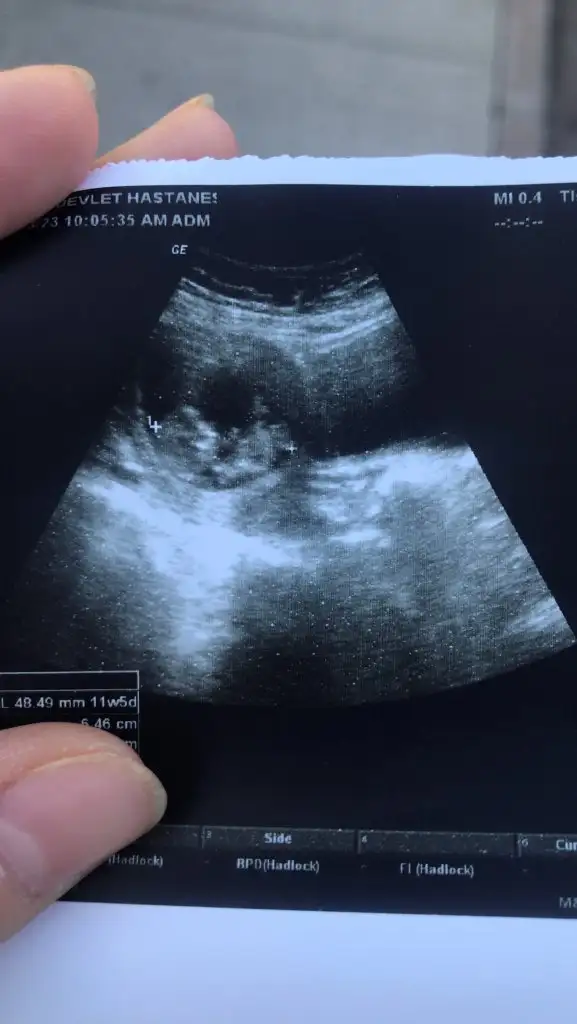

Banada tahminde bulunur musunuz 11 haftalık

Evet canım doktor sadece bu şekilde çekmiş oysaki çok güzel pozları vardı yavrumunPozisyonu uygun değill tek bu mu var